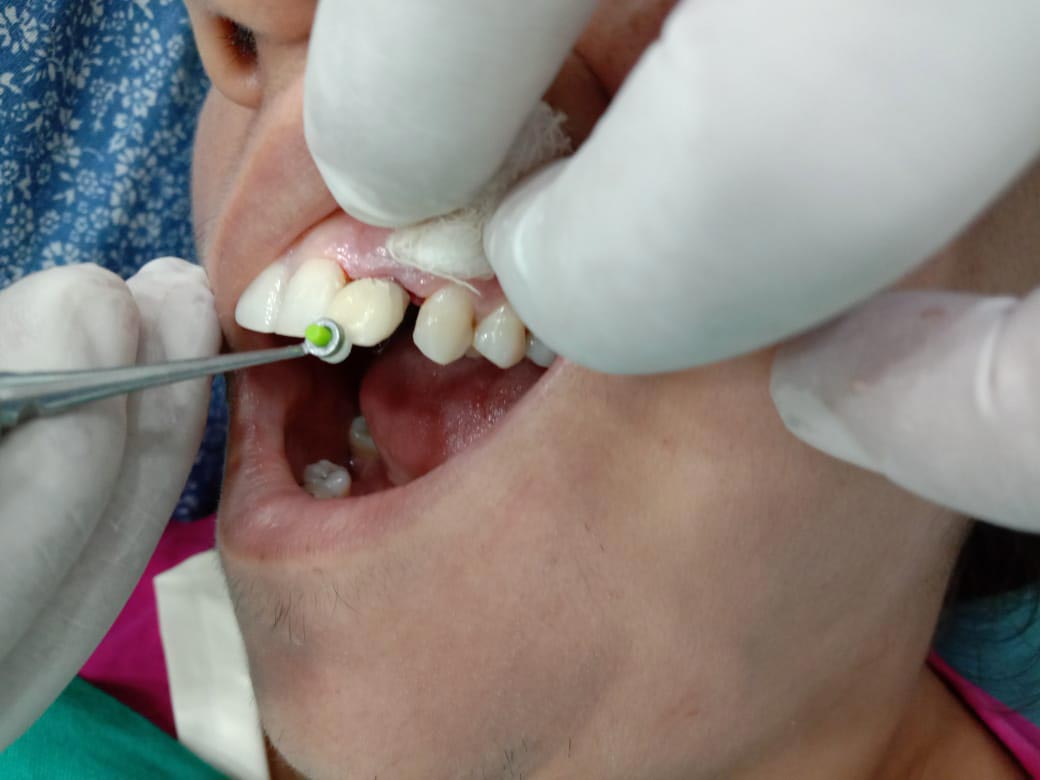

Step 5 : White socket abutment placed over implant.